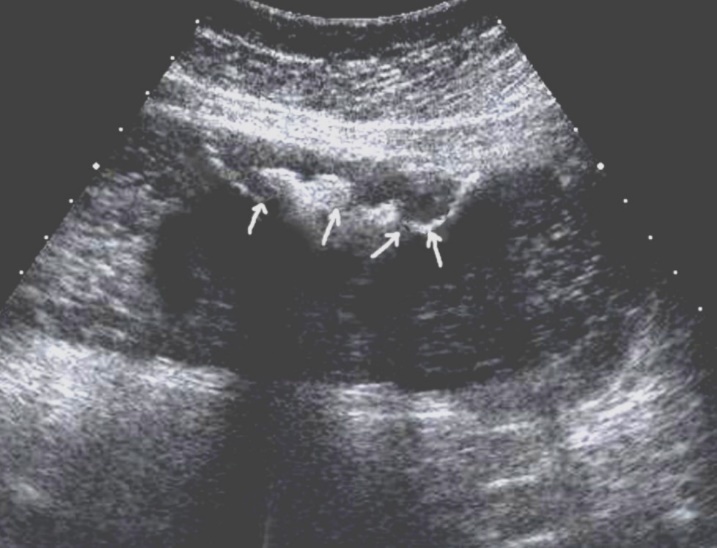

T3 stage of polypoid form was recorded in one case, ulcerative form – in 11 cases, infiltrative ulcerative forms – in 21 cases and diffused infiltrative forms – in 8 cases. The Sonographic features of infiltrative ulcerative form of gastric carcinoma was shown as local uneven thickening of the stomach wall with a length of up to several centimeters with intermittent images and ulceration of the mucosa (Figure 11). The Ulcerative form of gastric carcinoma was shown as a raised margins surrounded by a thickened gastric wall with irregular margins (Figure 12). Gastric carcinomas of diffuse infiltrative form is illustrated as a diffuse thickening of the muscle layer, a smooth contour, discontinuous mucosal image without ulceration and involvement of the serous membrane in the process (Figure 13).

Figure 11.Gastric carcinomas of ulcerating infiltrating forms in the anterior wall of the stomach body of stage T3.

Figure 12.Gastric carcinomas of ulcerating forms in the anterior wall of the stomach body of stage T3. Tumor is manifested with raised margins surrounded by a thickened gastric wall without clear margins.